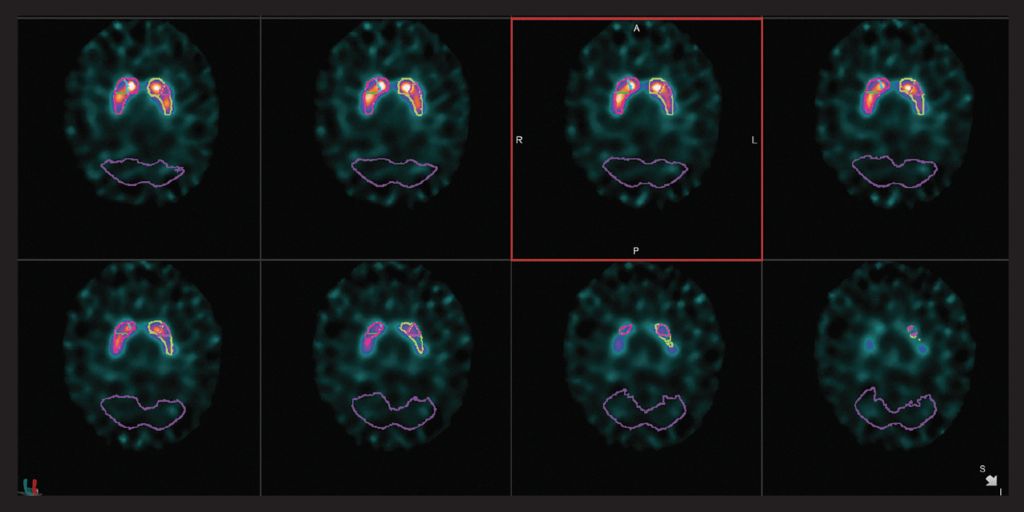

心臟

VERITON ? 采用我們成熟的CZT探測器技術(shù),可實現(xiàn)更好的協(xié)議優(yōu)化。考慮使用如此處所示的標(biāo)準(zhǔn)劑量的高分辨率2分鐘MPI采集,或選擇顯著更低的劑量同時保持短的采集時間。通過擴(kuò)展示蹤劑使用來檢查增加未來心臟實踐的方法。

VERITON ?獨有的360°設(shè)計產(chǎn)生3倍的體積靈敏度,為PET提供了真正的分子成像替代品。使用更具成本效益的示蹤劑結(jié)合新的更高分辨率SPECT圖像細(xì)節(jié)來擴(kuò)展您的核診斷服務(wù)。